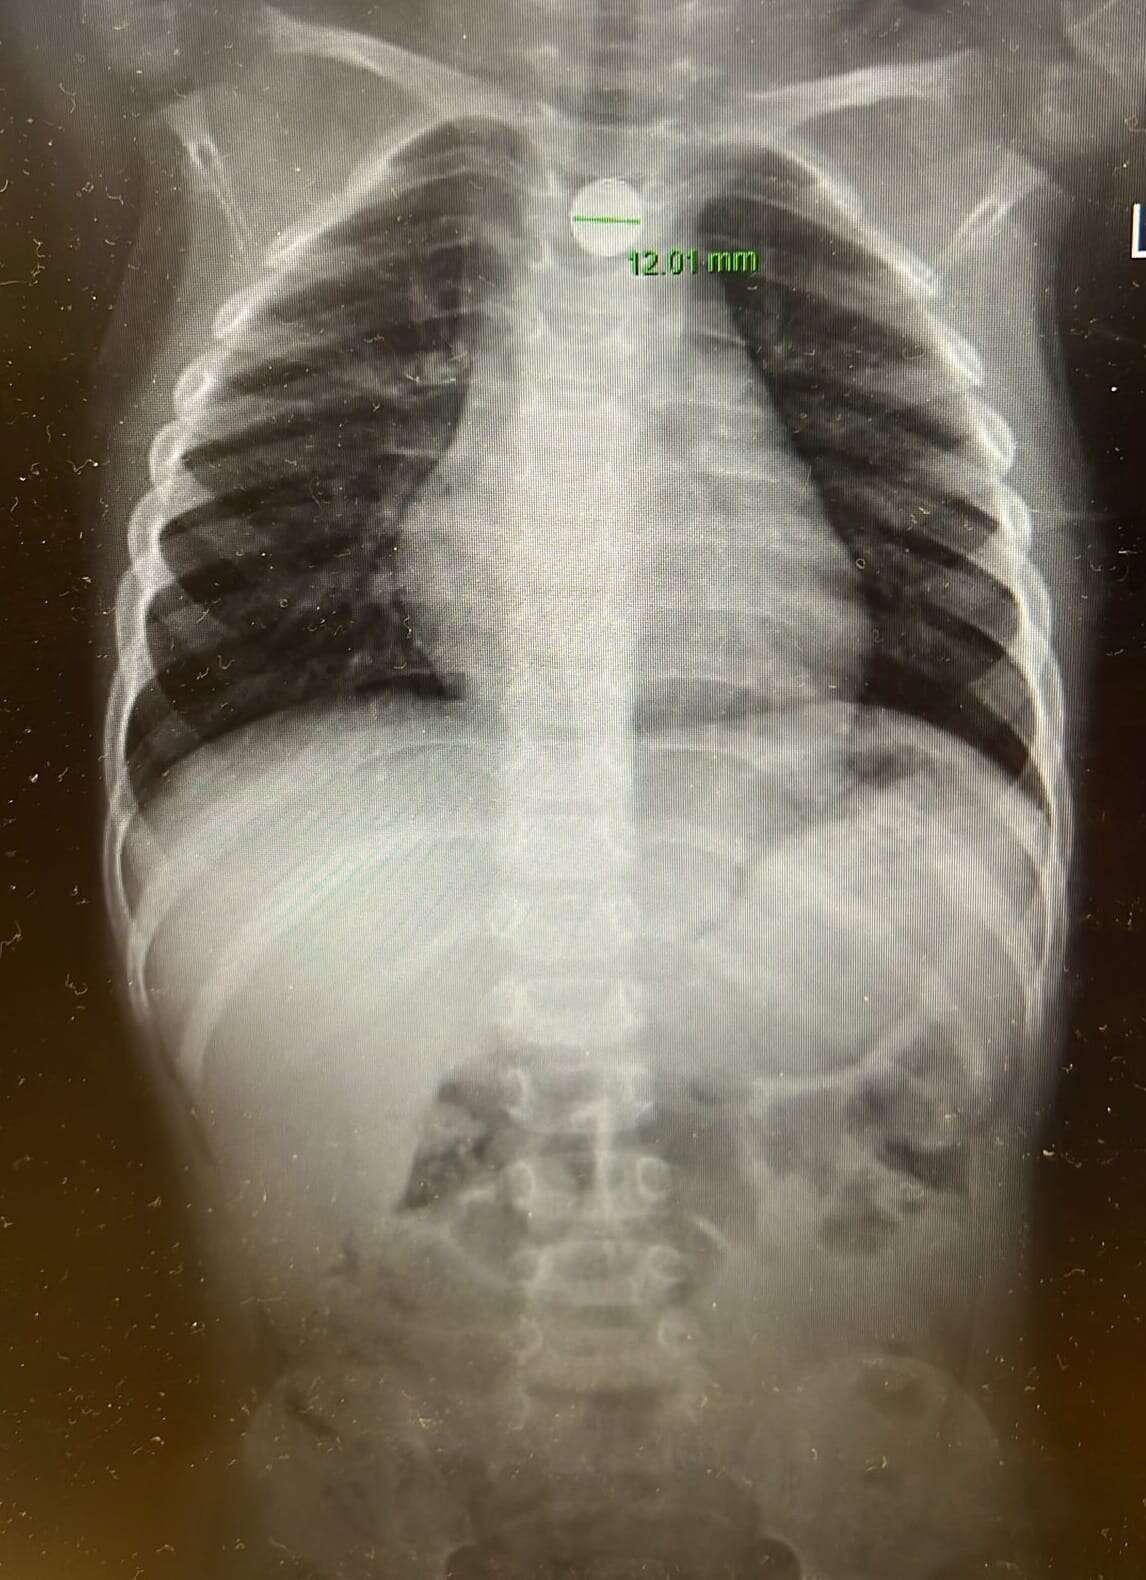

"אבא, בלעתי את זה": בן 3 הובהל לבית חולים עם סוללת דיסק בוושט‎

האירוע מסכן החיים נמנע רק בזכות תגובה מהירה של ההורים, שהביאו את הפעוט לבית החולים • אחרי בדיקה הסתבר שהדיסק נשלף מתוך צעצוע ודרש הליך גסטרוסקופי להוצאתו בשלמותו • לדברי הרפואים, התגובה המהירה מנעה נזק משמעותי